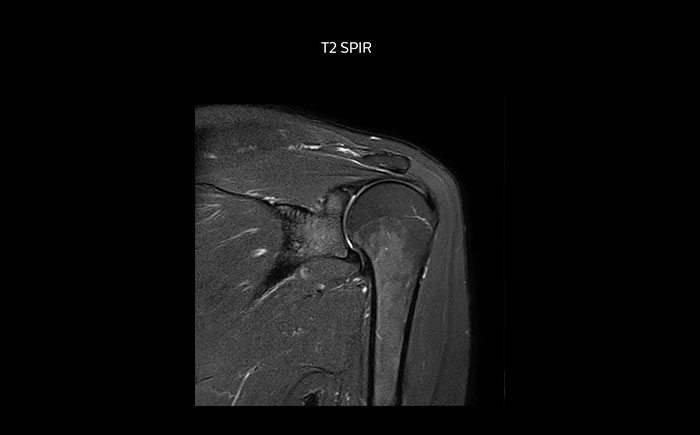

Shoulder MRI with high quality, large coverage

The Prodiva shoulder coil is very flexible and has large coverage, which makes good positioning easier, and that contributes to the superb image quality and high SNR that we get in our shoulder exams.

Shoulder MRI with high quality, T2 SPIR

Scan time 2:55 min, FOV 160 mm,

acq voxels 0.55 x 0.83 x 3.0 mm.